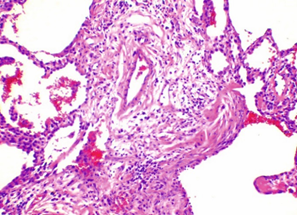

Комментарии: Эти патогистологические изменения обычно наиболее выражены в субплевральных и парасептальных зонах (Рис. 4). Интерстициальное воспаление обычно выражено умеренно, в виде очаговых инфильтратов, состоящих из лимфоцитов и плазматических клеток. В зонах фиброза могут встречаться так называемые фибробластические фокусы, состоящие из пролиферирующих фибробластов и миофибробластов (Рис. 5). «Сотовые» структуры представляют собой кистозные полости с фиброзной стенкой, обычно выстланные бронхиолярным эпителием, которые могут содержать слизь и клетки воспаления (Рис. 6).

Рис. 4. Обычная интерстициальная пневмония: участки фиброза в подплевральных и парасептальных зонах

Рис. 5. Обычная интерстициальная пневмония: миофибробластический фокус в месте перехода респираторной бронхиолы в альвеолы